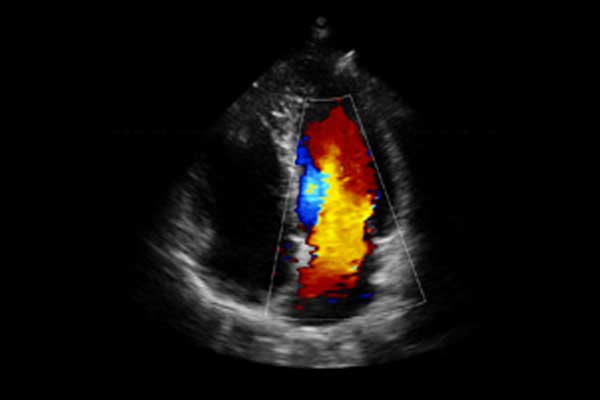

X3便携式彩色多普勒超声诊断系统是一款将小巧机身与卓越性能结合的便携产品。高度集成化的硬件模块,配合时尚前沿的人机工学设计打造了X3,如笔记本电脑般轻薄灵巧的机身、同时也赋予它突破体量限制的优异整机性能。轻便小巧,简单易用。图像清晰,X3可以随时随地满足您的使用需求。

X3搭载了丰富的探头群,可全面满足腹部、泌尿系统、浅表器官、妇科、产科、心脏及外周血管等常规领域应用。轻薄灵巧的主机机身、人性化的台车设计、实用的三探头扩展器、使得它无论在超声科还是在移动诊疗应用中都可以轻松应对。